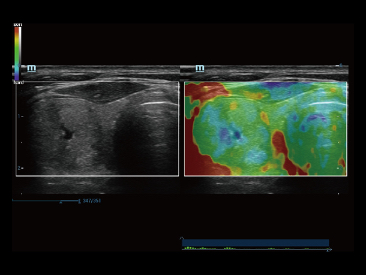

Desde que a empresa foi fundada, a Mindray est├Ī continuamente explorando novas maneiras de melhorar a confian?a no diagn├│stico. Alimentada pela mais revolucion├Īria tecnologia ZONE Sonography?, a nova plataforma Resona 7's ZST+ traz uma qualidade de imagem ultra-som a um n├Łvel superior por aquisi??o de zona e processamento de dados do canal.

Assim como o n├Łvel de qualidade de imagem premium, o Resona 7 tamb├®m melhora as capacidades de investiga??o cl├Łnica com o revolucion├Īrio Fluxo V para avalia??o hemodin?mica vascular e a aquisi??o de plano mais inteligente do conjunto de dados 3D para diagn├│stico CNS fetal. Combinando a opera??o mais intuitiva baseada em gesto de multi-toques e todos os recursos cl├Łnicos essenciais, Resona 7 est├Ī realmente conduzindo novas ondas na inova??o de ultra-som.